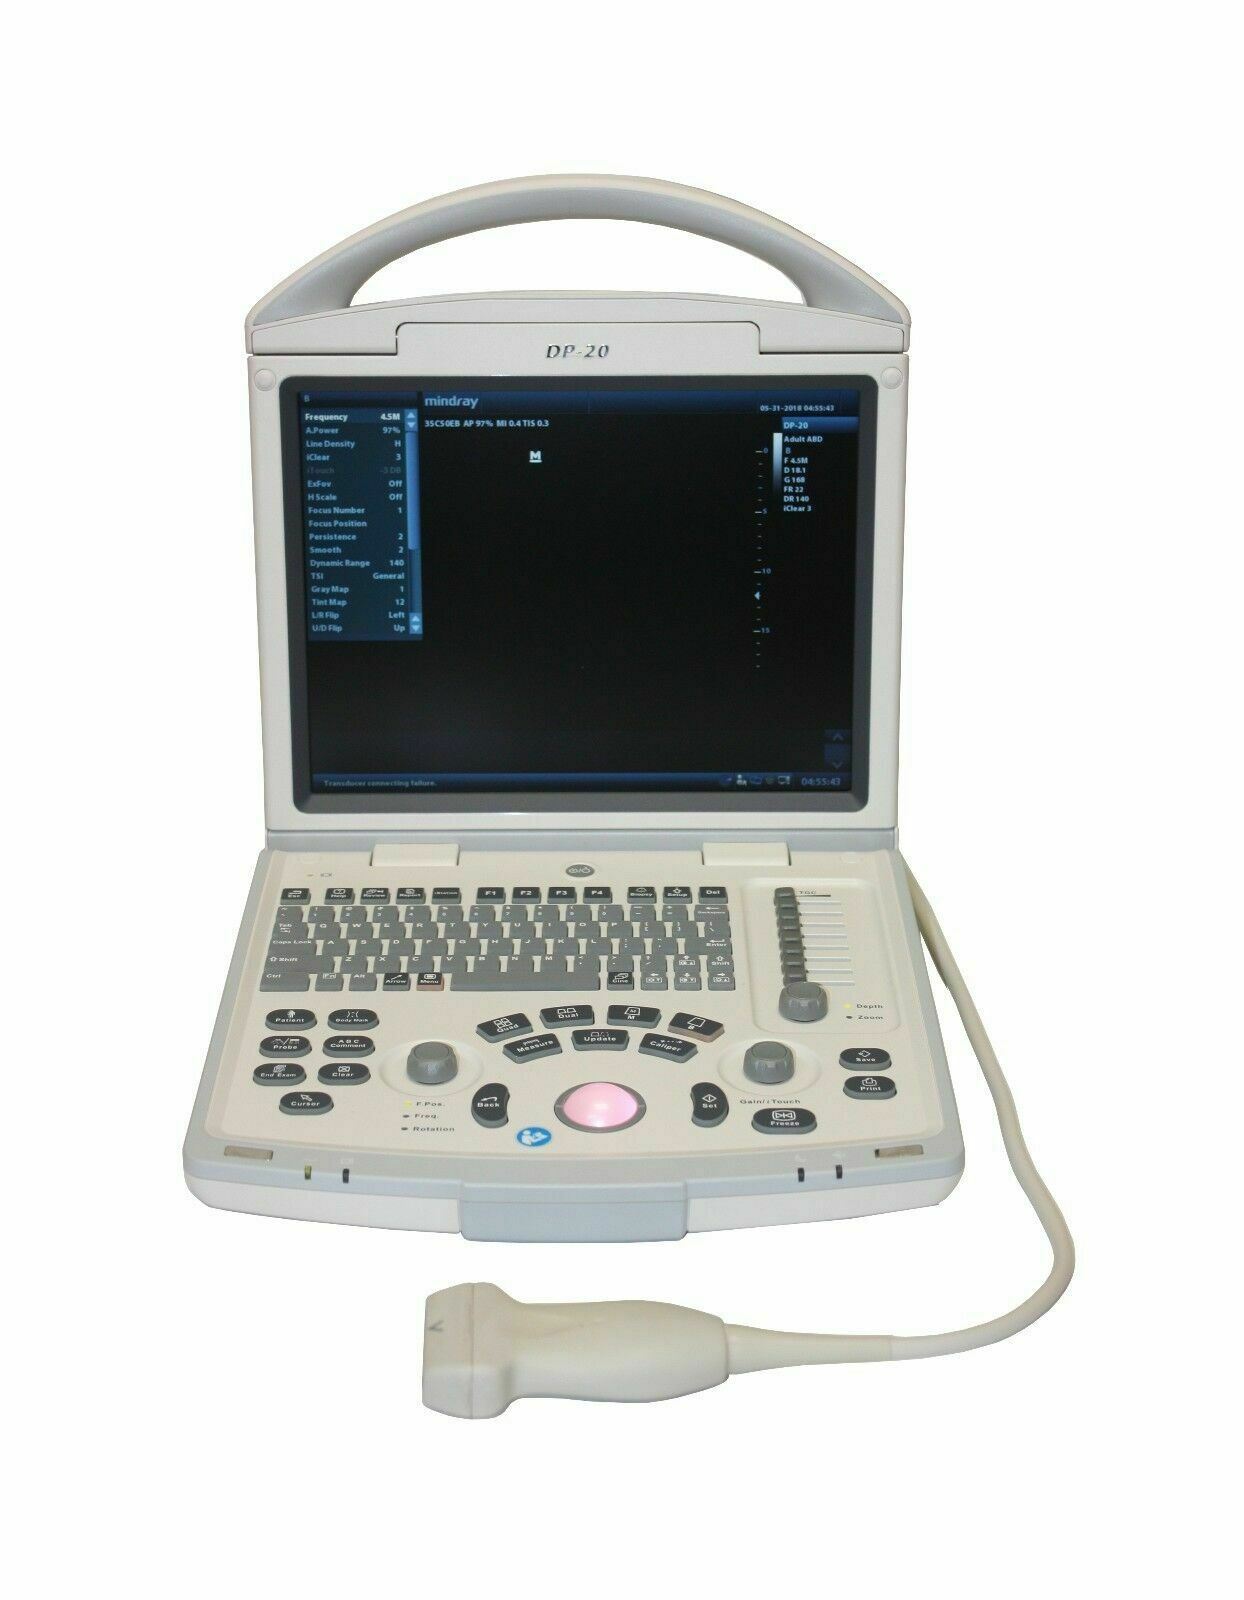

Veterinary Ultrasound K-DP-20Vet

Keebomed K-DP-20 is equipped with a best-in-class combination of performance and affordability. Provides the latest imaging technologies and convenient workflow options. Offers abundant measurement packages covering traditional ultrasound applications and emerging fields such as urology, MSK, and anesthesia.

- High resolution 12.1” LED with tilt functionality

- User-friendly keyboard and controls

- One transducer connector